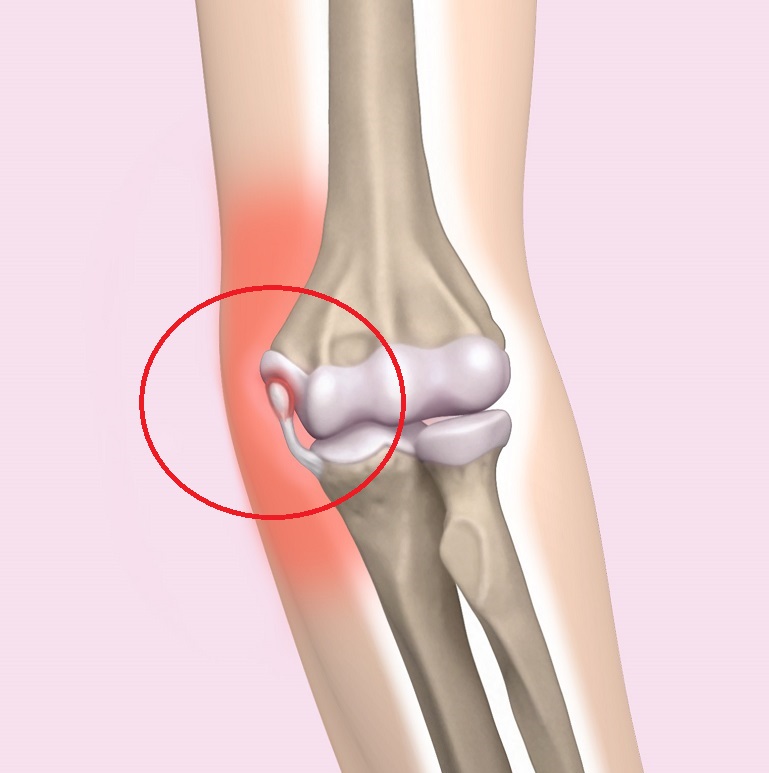

Thrower’s elbow is a sports disorder that is caused by baseball throwing, particularly overuse, which occurs in growing pitchers, and is mainly characterized by throwing pain in the throwing elbow of the medial side (Fig. 1), the outer side (Photo 1), and the elbow head (Photo 2). Symptoms often develop gradually and become chronic, so attention should be paid to elbow pain. The acceleration phase (acceleration) of throwing movements takes place in elbow flexion, valgus, and forearm supination. In the medial type, traction is exerted by the pronator flexor in throwing on the inside of the elbow, stretching the pronator muscles, the medial collateral ligaments, and the ulnar nerve, causing micro-damage inside the elbow. In severe cases, the medial epicondyle of the humerus develops avulsion fractures due to traction. In the lateral type, pressure is applied to the capitulum of the humerus and radius on the lateral side of the elbow, resulting in osteochondritis dissecans, with bone necrosis, defects, and loose bodies. The posterior type is in an elbow extension position during deceleration (follow-through), and traction forces are applied to the olecranon of the ulna, resulting in changes such as avulsion and stress fractures.

Figure 1 Medial type: Diastasis of the medial epicondyle of the humerus